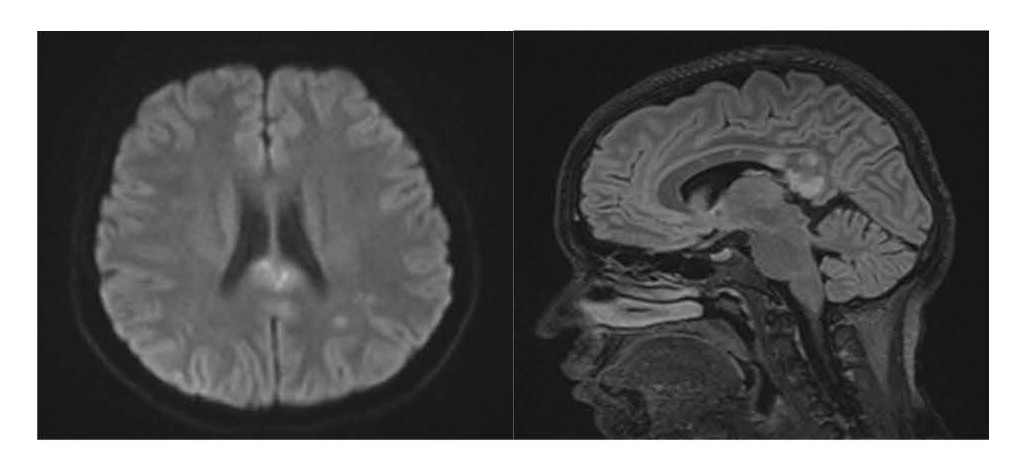

Magnetic Resonance Imaging (MRI) of the Brain shows multiple hyperintense T2 lesions in the corpus callosum with characteristic “snowball” appearance. DWI shows diffusion restriction in the centrum semiovale and parietal lobes, indicative of microinfarcts.

Figure 2. 07-Nov-2023 MRI: (1) DWI shows another diffusion restriction in centrum semiovale and parietal lobes suggested microinfarcts in white matter. (2) Sagittal FLAIR/T2 hyperintense lesions in the corpus callosum characterized by snowball-like lesion.